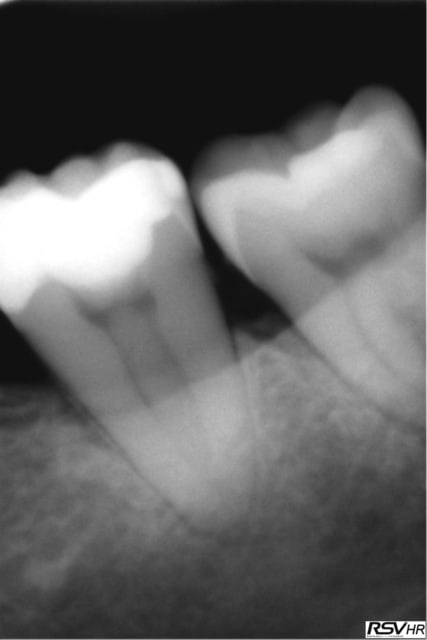

J'ai reposté quelques radios de biopulpectomies

RTE dans un précédent post...